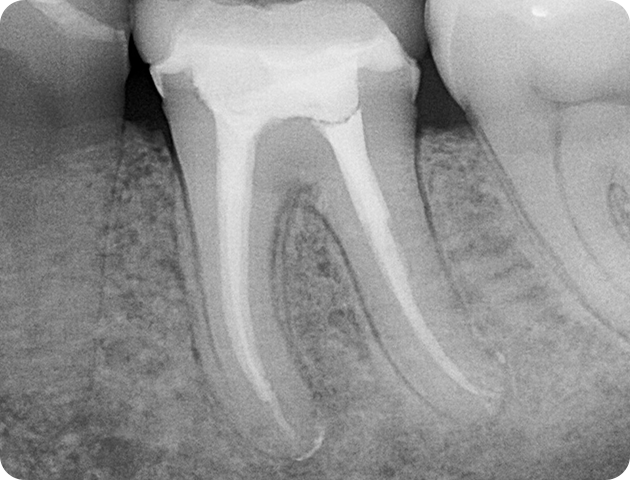

1. Diagnosis: X-rays and clinical examination to confirm pulp damage or infection.

2. Anesthesia: Local anesthesia is used to numb the area for a pain-free experience.

3. Access Opening: A small opening is made in the tooth to access the pulp chamber.

4. Cleaning the Canal: Infected tissue is removed, and the canals are cleaned and disinfected.

5. Filling the Canal: The space is filled with a rubber-like material (gutta-percha) and sealed.

6. Restoration: A temporary filling is placed, followed by a permanent filling or crown to restore full function and strength.